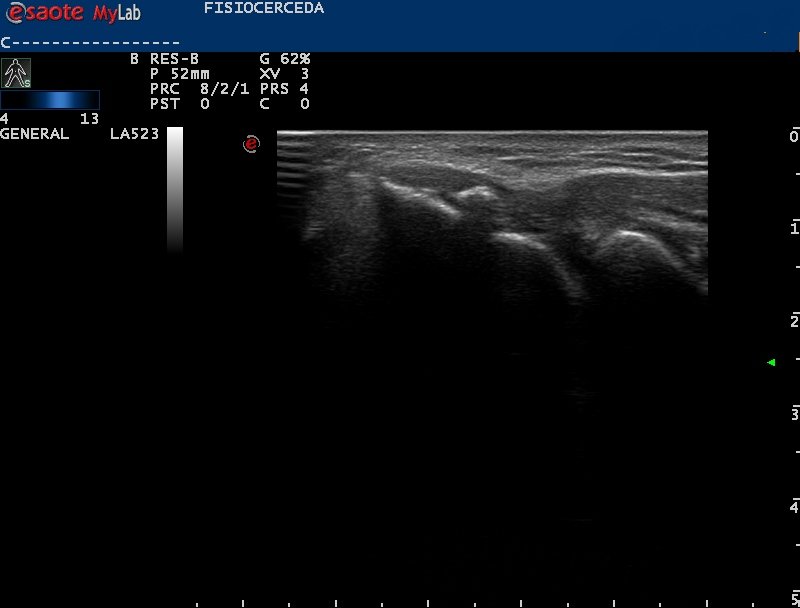

No todos los dolores de codo son producidos por degeneración o inflamación del tendón 😲. . Tras exploración ecográfica encontramos un artefacto hiperecoico con sombra acústica compatible con una calcificación y un tendón con ecoestructura normal. . #ecografia #fisiocerceda

No todos los dolores de codo son producidos por degeneración o inflamación del tendón 😲.

Tras exploración ecográfica encontramos un artefacto hiperecoico con sombra acústica compatible con una calcificación y un tendón con ecoestructura normal.

#ecografia #fisiocerceda